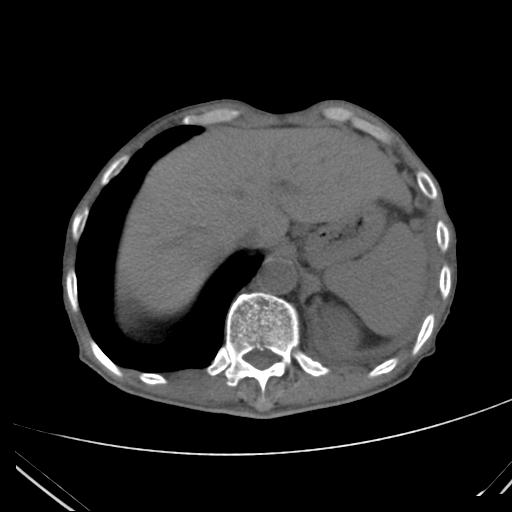

患者:男,81Y,纳差数月,左肺呼吸音减弱.

左侧胸廓塌陷,心脏纵隔左移,左肺可见大片小片状及多发低密度透光区,左侧胸腔背侧及侧胸壁见积液,右肺透光度增加。考虑:左肺干酪性肺炎并支气管内膜结核。建议结合临床,支气管镜检查。排除阻塞性病变

左侧胸廓塌陷,心脏纵隔左移,左肺可见大片小片状及多发低密度透光区,左侧胸腔背侧及侧胸壁见积液,右肺透光度增加。考虑:左肺干酪性肺炎并支气管内膜结核。建议结合临床,支气管镜检查。排除阻塞性病变。

左肺干酪性肺炎,不排除瘢痕癌可能。建议行纤支镜进一步观察。